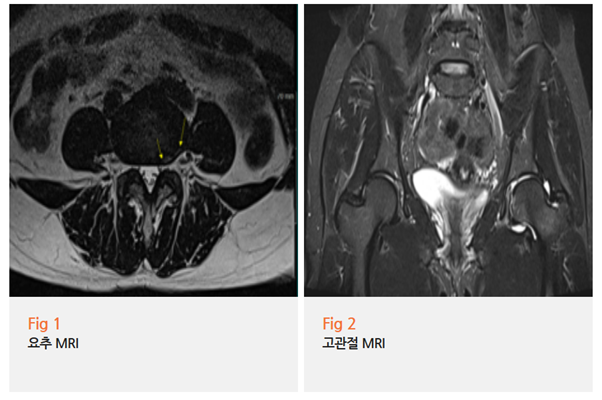

당일 MRI를 촬영하였고, 오후에 바로 결과가 나왔는데요.

예상대로였습니다.

1️⃣ 요추 4-5번 추간판에 경미한 퇴행성 변화

2️⃣ 좌측 고관절 부위에 명확한 염증 소견

3️⃣ 고관절 연골 주변 조직 손상 징후

환자분께 영상을 보여드리면서 차근차근 설명했습니다.

"보세요, 여기 이 부분이 정상보다 밝게 보이죠?

이게 염증이 있다는 신호예요.

그리고 이쪽 연골 주변도 약간 불규칙하게 보이는데,

이게 바로 충돌이 반복되면서 생긴 손상입니다."